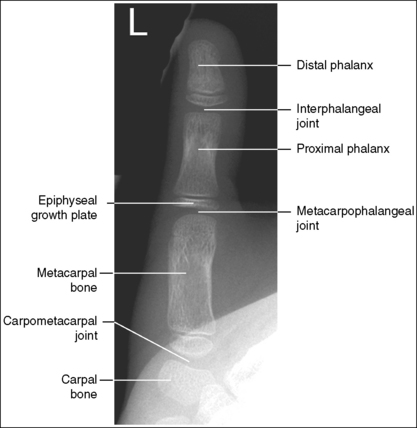

See Figures 4-12 and 4-13 and Box 4-5.

The first digit demonstrates an AP projection. The concavity on both sides of the phalangeal and metacarpal midshafts is equal, as is soft tissue width on both sides of the phalanges.

• An AP projection is accomplished by internally rotating the patient's hand until the thumb is positioned in an AP projection (Figure 4-14). The thumbnail can be used as a reference to determine when the thumb is truly placed in an AP projection. The nail should be positioned directly against the IR and should not be visible on either side of the thumb. A nonrotated AP thumb projection demonstrates equal concavity on both sides of the phalangeal and metacarpal midshafts, as well as equal soft tissue widths on both sides of the phalanges.

The IP, MP, and carpometacarpal (CM) joints are visible as open joint spaces, and the phalanges are not foreshortened.

The MP joint is at the center of the exposure field. The distal and proximal phalanges, the metacarpal, and the CM joint are included within the collimated field.

• Center a perpendicular central ray to the MP joint, which is located where the palm's interconnecting skin attaches to the thumb, to place it in the center of the image. Open the longitudinal collimation to include the distal phalanx and CM joint. Transversely collimate to within 0.5 inch (1.25 cm) of the thumb skin line.

• Pediatric bone age assessment. A bone age image is obtained to assess the skeletal versus the chronologic age of a child. Because bones develop in an orderly pattern, skeletal age may be assessed from infancy through adolescence. Illness, metabolic or endocrine dysfunction, and taking certain types of medications and therapies are all reasons why a pediatric patient's skeletal and chronologic age may not correspond. A left PA hand and wrist projection is typically the image of choice because bony developmental changes are readily visible and easily evaluated. For skeletal age to be evaluated, the phalanges, metacarpals, carpals, and distal radius and ulna must be included in their entirety (see Figure 1-130).